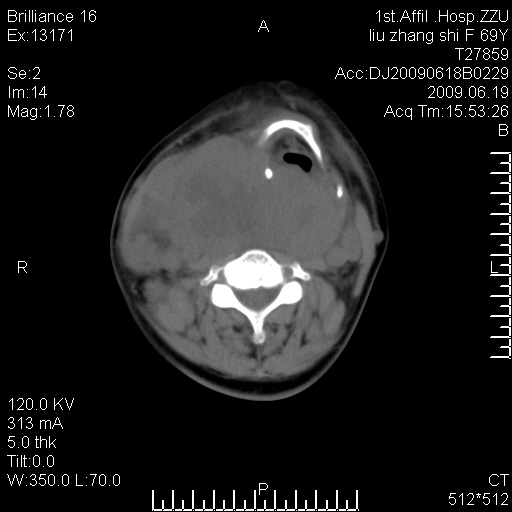

标题: CT26782:女,69岁,颈部占位,3天后公布病理结果。

【病理证实系列】女,69岁,颈部占位,有病理结果,3天后公布。(由于病例时间较久,临床资料不全,请网友见谅)本系列将有几百种常见、少见及罕见病例,均经病理证实。病例资料来自郑州大学第一附属医院。与网友共享,本人有空就发。

甲状腺癌并颈部淋巴结转移。感谢楼主的良苦用心,谢谢。

甲状腺癌并颈部淋巴结转移。

需与鼻咽癌鉴别!

支持甲状腺癌广泛侵及周围结构并颈部淋巴结转移。

鉴别:淋巴瘤、恶性神经源性病变、恶性纤维组织细胞瘤。

病理结果:颈部非霍奇金淋巴瘤。

右侧甲状腺确实有问题